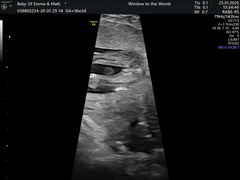

I'm 16+3 and went today privately to have my gender scan. I've had put in my head since day one that we'll be having a boy, today at the scan we got told we'd be having a little girl. We're very much in shock because all we've been convinced by people is it's a girl 🤣. We're happy and we didn't mind the gender as long as they were heathy. The only thing that's on my mind was that it took a while for the sonographer to figure out the gender and I had to cough a few times to get her to budge! Me and oh could have sworn we saw a little penis in the photos but the sonographer saw the three lines for a burger for a girl. I've attached the scans and the photos we thought were a boy. Is it the placenta that we saw? I feel awlful questioning it and we are happy but would be happy to hear your thoughts!